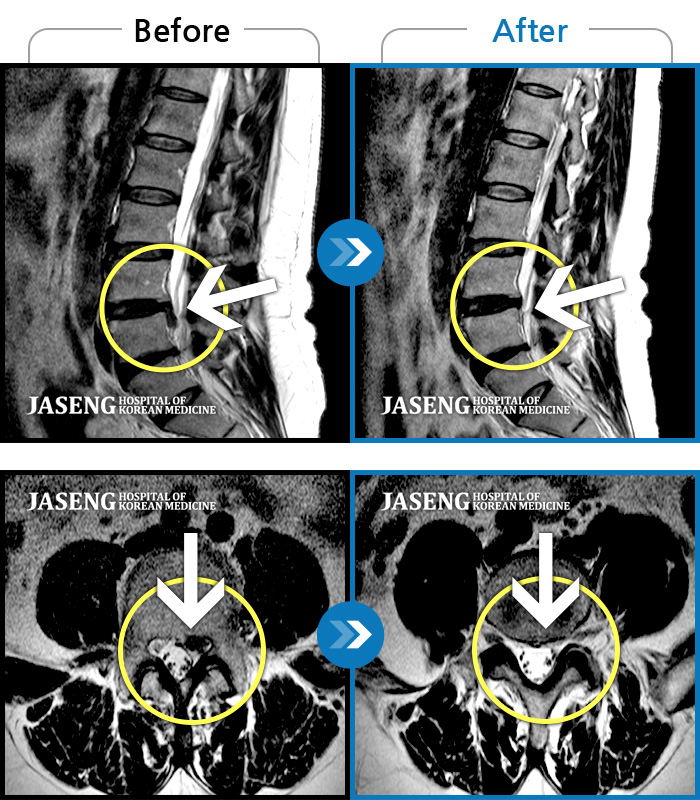

내일이면 퇴원이다. 3월부터 주위에서 허리통증 치료 잘 한다는 통증의학과ㆍ신경외과ㆍ정형외과 병원 3곳을 돌아다니며 허리 신경주사 12번 ,도수치료 10번, 물리치료 등등 정알 여러가지를 받았다. 그러나 치료와 처방 받은 진통제만으로는 일상생활을 하기가 많이 힘들었다. X레이 사진으로 확인한 척추 전방전위증은 결국은 수술을 받아야 한다고 하였다.

전방전위 대해 알아보다가 자생병원 홈페이지에서 김상돈 병원장님이 임상치료 하셨다는 것을 보고 잠시의 망설임도 없이 전화 예약하고 입원 하게 되었다.

MRI 검사로 정확한 진단을 시작으로 병원장님의 치료를 2주간 받았다. 친절한 설명과 따뜻한 배려로 정말 마음 편하게 치료 받을수 있었다.